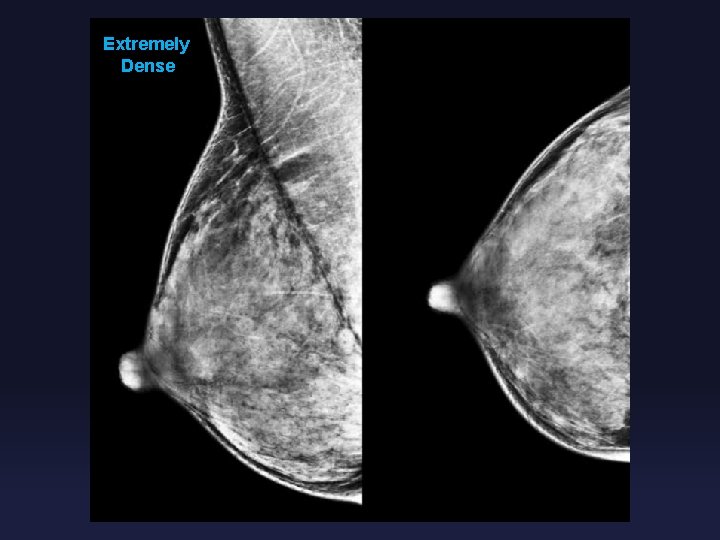

Controversies in Screening Mammography RISKS § False negative exam (“Happy Gram”) § Increased breast density makes mammographic detection of malignancy more difficult § Breast density = proportion of fat to gland § Almost entirely fatty § Scattered fibroglandular densities § Heterogeneously dense which may obscure small masses § Extremely dense

Extremely Dense

Controversies in Screening Mammography RISKS § False negative exam (“Happy Gram”) § Dense breasts § Masking effect § Digital Mammography improves false negative rate compared to screen film § Increased risk of breast malignancy with increased breast density § Heterogeneously dense: RR 1. 2 § Extremely dense: RR 2. 1 § Supplemental screening?